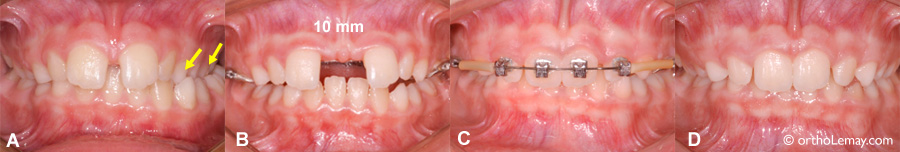

(A) Lorsqu’un espace (diastème) est déjà présent avant le début de l’expansion maxillaire rapide, l’ouverture de l’espace interdentaire sera plus importante. Occlusion croisée postérieure droite (flèches).

(B) L’espace initial de 2.5 mm a augmenté à 10 mm lors de l’immobilisation de l’appareil d’expansion.

(C) Un tel espace ne se refermera pas complètement seul, mais il est possible de le fermer à l’aide d’appareils fixes. Cette correction peut être faite pendant que l’appareil d’expansion est en bouche une fois les tours d’activation terminés.

(D) Résultat après la fermeture du diastème, l’enlèvement des appareils et la récidive postérieure de la surcorrection.